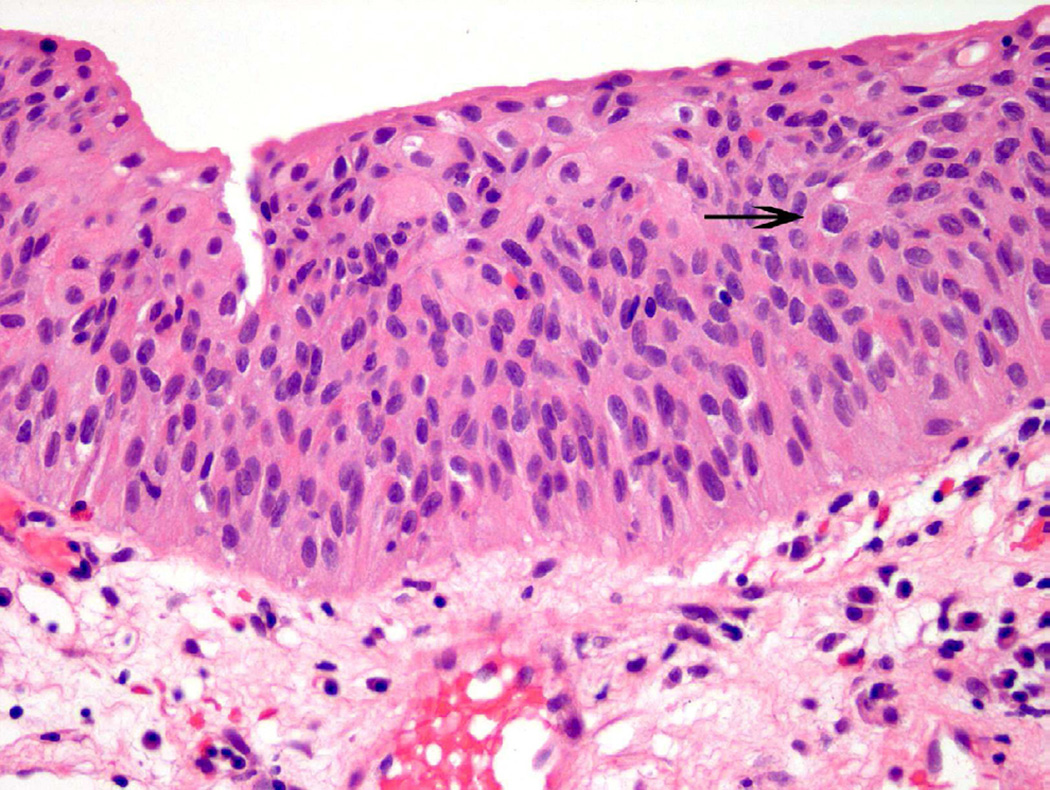

Urothelial dysplasia is considered to represent early pre-neoplastic/neoplastic change, with histologic features beyond that considered in the spectrum of benign or reactive urothelium9. In dysplasia, the thickness of the urothelium can be variable, but umbrella cells are usually present. Features of cellular crowding, multiple nucleoli, and mild hyperchromasia are common in this diagnostic category (Fig. 5)10. The diagnosis of ‘dysplasia’ is used when some, but not all, of the criteria necessary for urothelial carcinoma in situ (CIS) are met. Currently, further sub-classification of dysplasia into ‘mild’ or ‘moderate’ grade is no longer commonplace, whereas ‘severe dysplasia’ is generally considered CIS.

Figure 5.

Dysplasia is a subjective diagnosis. In this case, variable nuclear size, mild cellular disorganization and occasional abnormal nuclear contours (arrow) support the diagnosis.